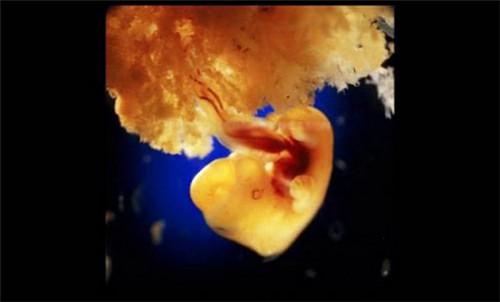

40天,外层胚胎细胞与松散的子宫表层融合,形成胎盘

6495663725.jpg

第8周

6075391843.jpg